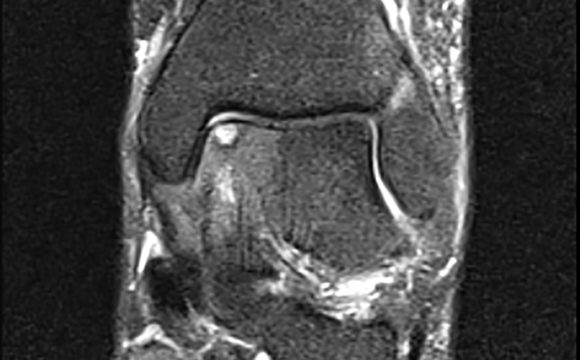

Osteochondral Defect

In Ankle Surgery, Osteochondral Defect